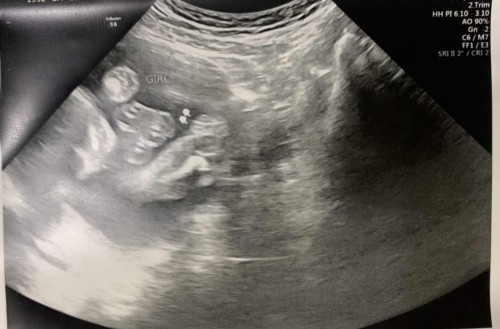

Ultrasound

Confirm na po ba talagang Baby Gurl? π€£

yup baby girl